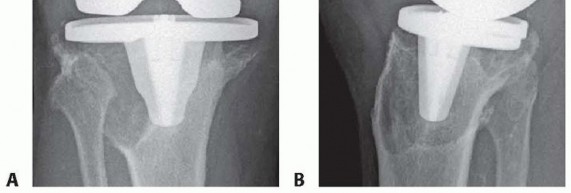

Structural allografts are particularly susceptible to specific failure modes, including nonunion at the host graft interface, late graft resorption, and structural fracture of the allograft. Because bulk allografts are avascular and incorporate slowly via creeping substitution, they remain mechanically vulnerable for years postoperatively. Infection is another catastrophic complication, as the massive avascular graft serves as a perfect nidus for biofilm formation.

| Allograft Nonunion / Resorption | 8% - 15% | Poor host bed preparation; cement interposition at the host-graft interface; inadequate mechanical stabilization; immunologic rejection (rare). | Revision with highly porous metaphyseal cones or sleeves; tumor megaprosthesis if remaining bone stock is critically depleted. |

Management of these complications requires a highly individualized approach. If a structural allograft fails via late resorption or nonunion but the joint remains uninfected, revision utilizing highly porous metaphyseal cones or sleeves is the modern salvage strategy of choice. These porous metals provide immediate biological fixation via osteointegration and do not rely on the creeping substitution required by allografts. In cases of catastrophic failure with complete loss of the proximal tibial metaphysis and collateral ligament attachments, a hinge knee tumor megaprosthesis may be the only viable salvage option to avoid amputation.